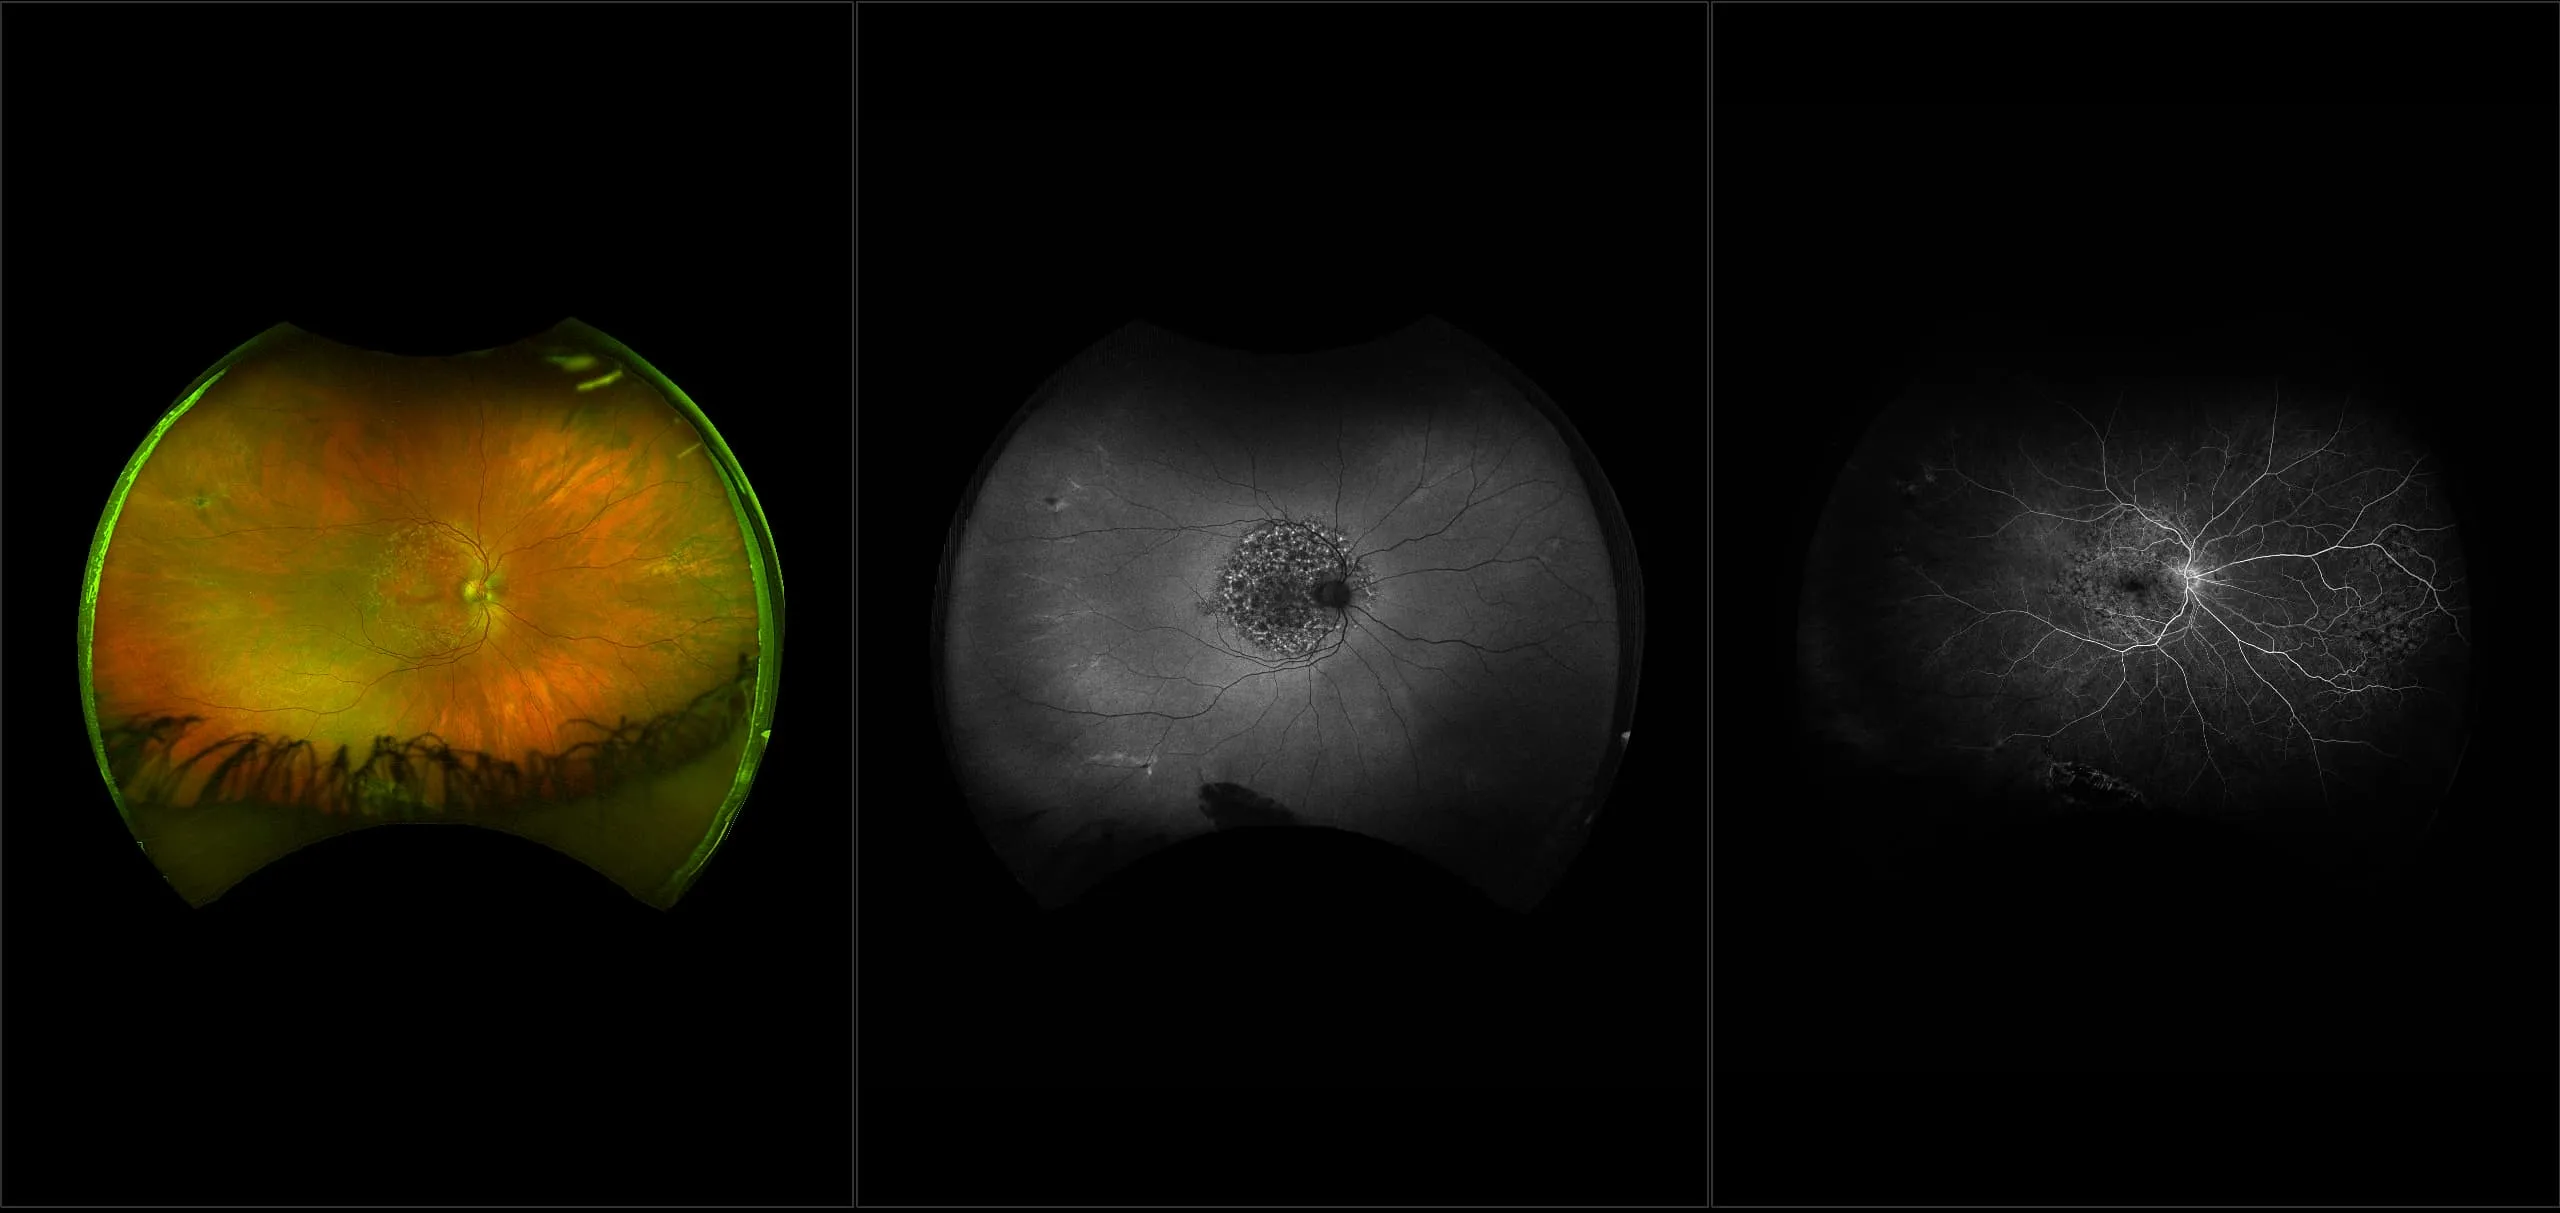

optomap® Recognizing Pathology

This material is designed as a searchable reference resource to support clinical decision-making. The information contained here should be used as general guidance when viewing optomap and OCT images from Optos devices. The differential diagnosis should be made under the direction of the responsible physician. These images were taken on the latest ultra-widefield optomap devices.

The Cases and Images

optomap Recognizing Pathology is searchable by pathology and/or optomap image modality. You may search by multiples of each selection. Each individual case is represented by the accompanying thumbnail image. Most cases include several different optomap image modalities. To view a full description of the case, please click on the thumbnail. Each image in the case will be made available through our OptosAdvance software which provides multi-dimensional visualization of digital images to aid in the analysis of anatomy and pathology. Support and pathology definitions can be found by selecting one of the buttons, above. Should you have questions, please complete the form below.